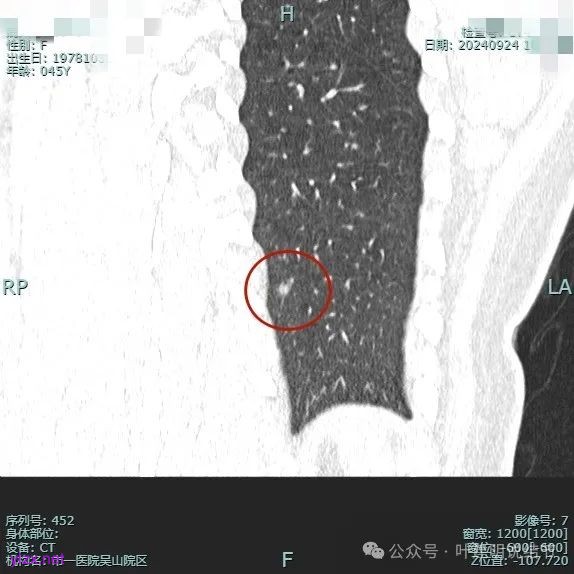

病灶1:

病灶是混合密度,边缘少许淡磨玻璃,灶内不太致密,表面不平,血管征有,但说不上明显异常增粗。

病灶紧贴叶间裂,而且感觉跨过肺叶,部分影响到上叶了,病灶本身密度虽实性为主,但是不太致密,有点松散的感觉。

总体实性部分密度较高,而磨玻璃部分密度较低,且瘤肺边界欠清,关键是跨叶间裂生长,这与肿瘤似乎不容易解释些。

毛刺有但不太锐利,磨玻璃有但偏淡,实性为但不太致密,叶间裂与之关系密切,病灶跨叶生长。

上图显得与肿瘤较为符合,但跨叶生长的话,侵袭力应该较强,可她这病灶较刚发现时进展并不太明显。

上图层面也较符合恶性,血管进入明显,有浅分叶的样子,整体觉得有一定收缩力与膨胀感。

病灶表面不平,混合密度,磨玻璃成分较淡。